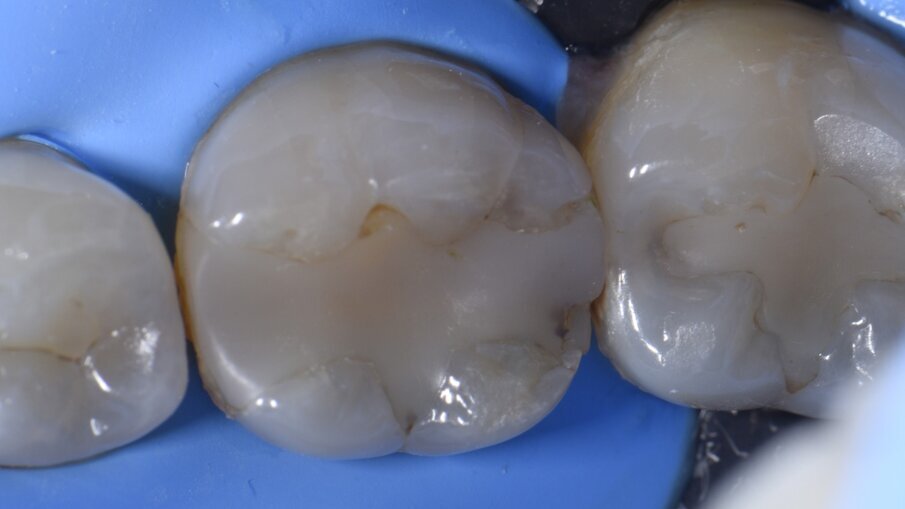

Un fallimento parziale del trattamento è stato diagnosticato sul dente 19 rispetto a un precedente restauro in composito (Fig. 1). Il paziente da un mese si lamentava di una sensibilità al morso. Le preoccupazioni primarie riguardavano sia il micromovimento del vecchio restauro, ma anche la possibile presenza di fratture o microfratture, che potevano essere chiarite solo tramite un restauro esplorativo.

Il paziente è stato anestetizzato utilizzando una Lidocaina al 2% con epinefrina 1:100.000, dopodiché è stata posizionata una diga di gomma (NicTone). Eseguita la preparazione, il restauro è stato rimosso insieme a praticamente tutta la linea sottostante per permettere la valutazione del pavimento pulpare. Non sono state identificate crepe o microfratture ed è stato utilizzato un rilevatore di carie (rilevatore di carie, Kuraray) per garantire gli endpoints di rimozione della carie (Fig. 2). I margini sono stati smussati (0,5-1,0 mm) poiché più il margine è vicino alla superficie della cavità dell’apice della cuspide, più si tenterà di legarsi lateralmente ai prismi di smalto, mentre è più efficace legarsi alle estremità. La smussatura consente l’esposizione trasversale dei prismi e una migliore efficienza di mordenzatura e adesione. La microabrasione ad aria è stata eseguita isolando il dente adiacente con una striscia di metallo seghettato e utilizzando ossido di alluminio da 27 micron (Prep Start, Danville Engineering) a 2-3 bar di pressione. Questa operazione è stata completata prima del posizionamento di qualsiasi sistema di matrici sezionali poiché l’irruvidimento tipico della matrice unito all’uso di un adesivo automordenzante contenente 10-MDP (legami 10-MDP a metalli non preziosi) vedrà una rimozione della matrice più difficile dopo la costruzione della parete, spesso con residui del colore del rivestimento in Teflon della fascia lasciata aderente al restauro.

Come primo passo, si è scelto di ricostruire la parete mesiale (Fig. 3). Microstrati di un A2 fluido (Majesty esthetic, Kuraray Noritake) sono stati posizionati dopo un approccio di tipo total etch con MPa Bond (Clinicians Choice). A questo è stato permesso di disaccoppiarsi con il tempo per consentire la maturazione e l’ibridazione finale del legame alla dentina per il massimo rafforzamento del legame microtensile. La parete prossimale è stata ricostruita in strati orizzontali con incrementi di 1 mm in modo occlusale come prescritto dalla tecnica di Nikolaenko et al., consentendo valori massimi di forza di adesione microtensile. Dopo la polimerizzazione per una durata di 20 secondi, il gruppo della matrice sezionale è stato rimosso, l’anatomia del punto di contatto e la forza valutate con il filo interdentale prima dell’assemblaggio della matrice per ricostruire la parete prossimale in modo simile (Fig. 4). A seguito della costruzione della parete distale e dei relativi controlli, si è creata una situazione di Classe 1, priva di anelli di tensione e altri accessori che possono impedire l’accesso per la stratificazione occlusale (Fig. 5). La preferenza dell’autore di ricostruire una parete alla volta con matrici mesiali e distali posizionate separatamente attraverso il processo è in contrasto con i risultati della forza di contatto prossimale (PCS) di Sabre et al., che promuovono il posizionamento simultaneo di assemblaggi mesiali e distali. L’autore ritiene che il primo metodo sia più prevedibile soprattutto su denti più piccoli come i premolari, dove possono esserci difficoltà fisiche con il posizionamento simultaneo di matrici mesiali e distali a causa della necessità di sovrapporre Slick Bands insieme al rischio di comportamento a fisarmonica della matrice.